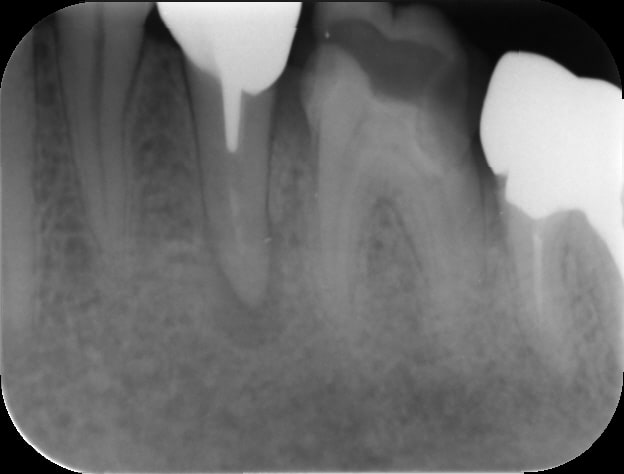

radio de contrôle apres pose d IC la semaine passée , jusque là ça va :-) pas évident sur 1 dent toute seule en terminal

Eri l00uyw - Eugenol